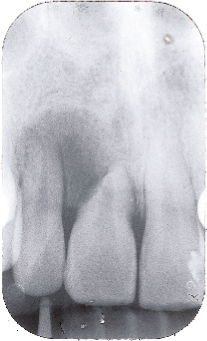

Các loại răng dư Tuberculate ( tạm dịch là dạng củ) có nhiều hơn một chỏm hoặc củ. Hình dạng của nó thường là hình ống và được bao bọc trong ống. Sự hình thành chân răng chậm so với các răng cửa vĩnh viễn. Răng dư Tuberculate thường theo từng cặp và thường nằm trên cung hàm của các răng cửa giữa. Nó hiếm khi nhú lên và thường liên quan đến tình trạng chậm mọc răng cửa (Hình 5 và 6).

|

Hình 5: Cặp răng dư tuberculate liên quan đến rối loạn mọc răng |

Hình 6: Rối loạn mọc răng của răng cửa giữa hàm trên liên quan đến răng dư tuberculate được minh họa ở hình 5 |

Sự hiện diện răng dư là nguyên nhân phổ biến nhất gây không mọc được răng cửa giữa hàm trên. Nó cũng có thể là nguyên nhân chậm thay răng sữa. Vấn đề thường được chú ý với việc mọc răng cửa bên hàm trên cùng với tình trạng không mọc được một hoặc cả hai răng cửa trung tâm (Hình 5 và 6). Răng dư ở các vị trí khác cũng có thể gây không mọc được các răng lân cận.